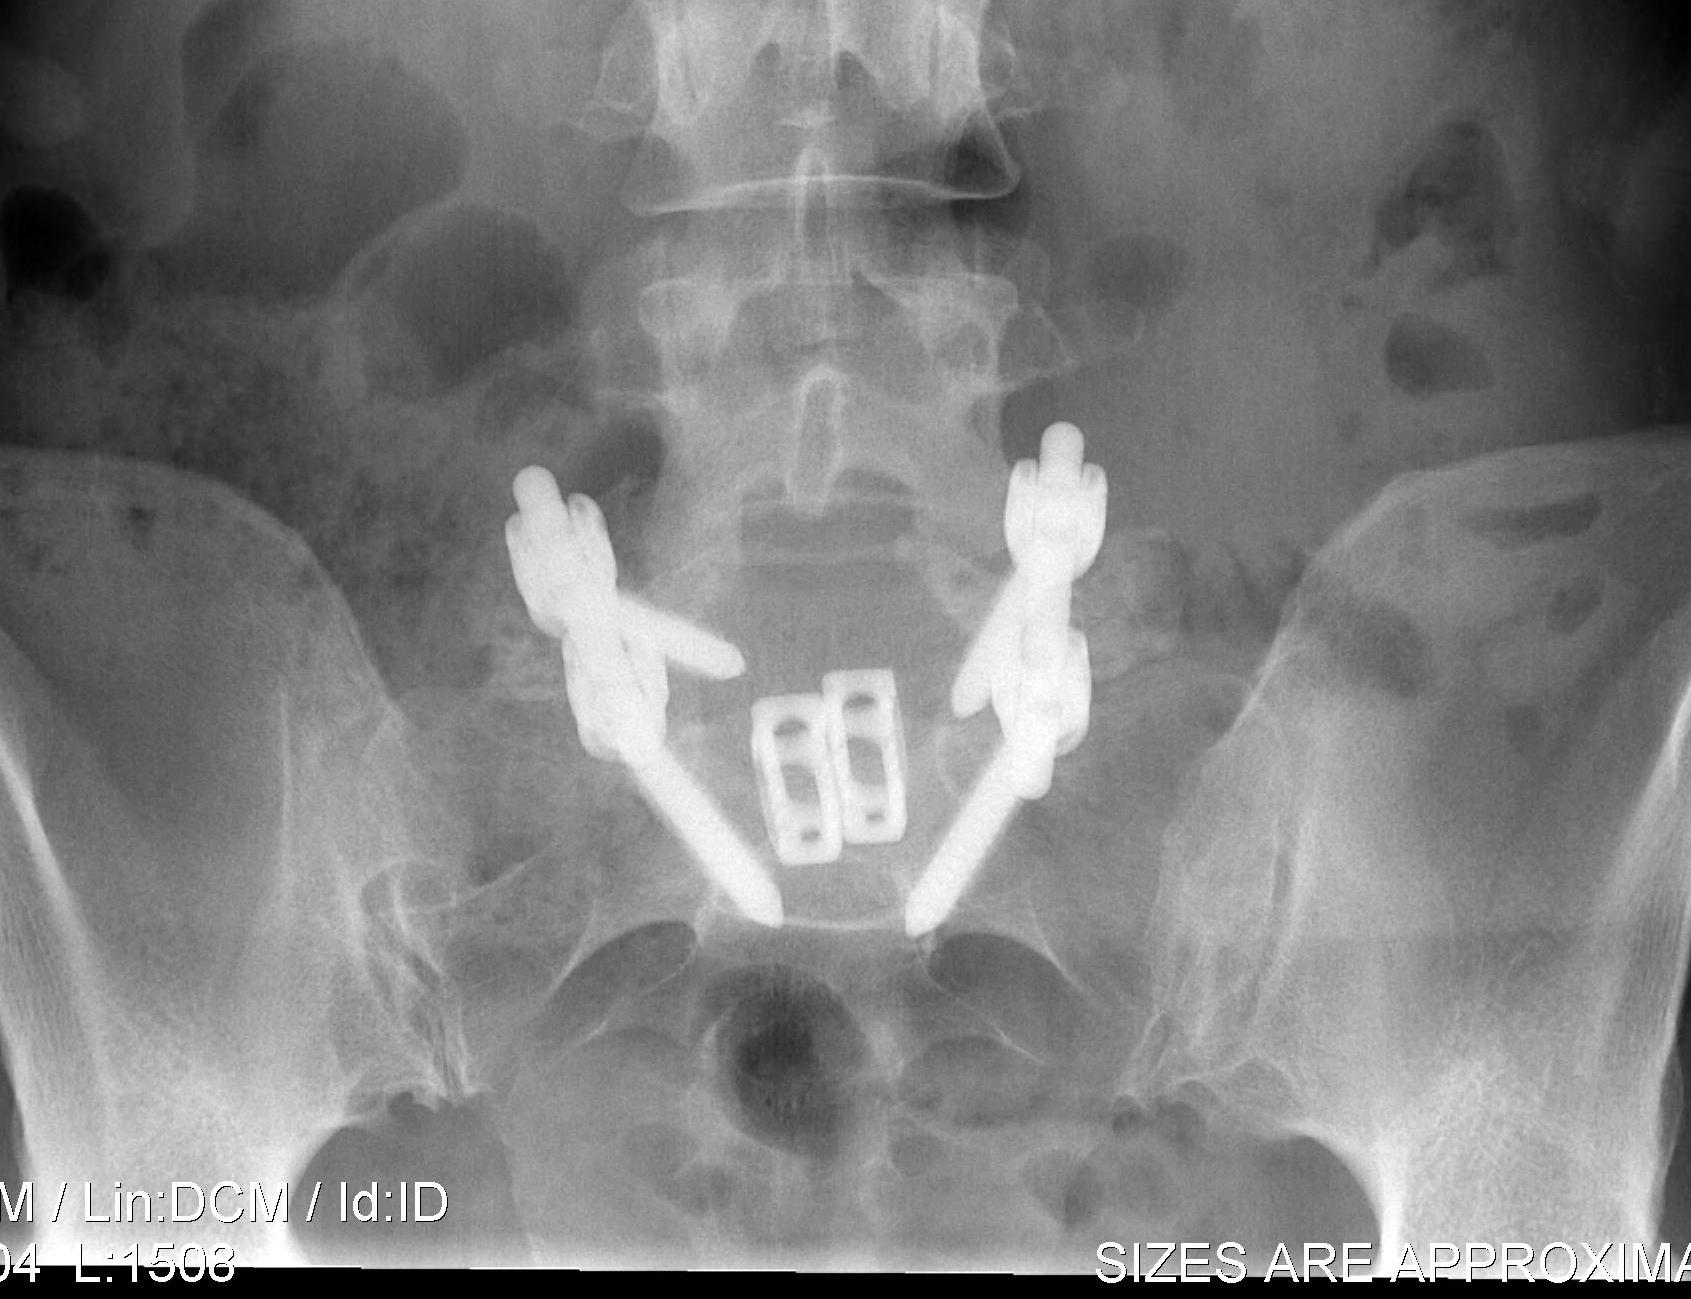

ALIF

Concept

- anterior approach + complete discectomy and graft

Disc Replacement

- maintain small degree of motion

- prevents adjacent level degeneration